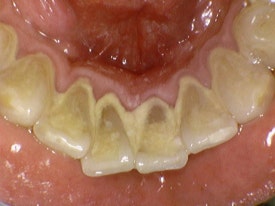

위 사진은 본원에서 진행한 스케일링 전 후 사진입니다.

보기만 해도 너무너무 시원하죠!